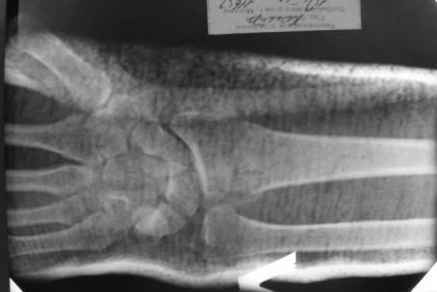

Уважаемые коллеги.Прошу обсудить случай лечения перелома дистального метаэпифиза лучевой кости. Ситуация скандальная и крайне неблагоприятная. Больная с патологической обстоятельностью мышления, склонностью к сутяжничеству, патологическими умозаключениями, не поддающимися коррекции (см. психиатрию, правда офиц. диагноза нет). В данном случае есть ряд ошибок с нашей стороны, прежде всего в отношении качества ведения документации (за что получил административное взыскание, по делом мне дураку). В остальном- придерживались в лечении подхода классический советской школы. Так как умную операцию…… сами знаете… 15.12- перелом луча в Москве. Там же репозиция, гипс. Дальнейшее лечение у нас в ЦРБ. 20.12.- вторичное смещение в гипсе21.12- под внутривенным наркозом- репозиция, гипсовая лонгета. Дальше начинается самое интересное. После репозиции больная заявила, что я (репозицию делал я) порвал ей все связки в суставе, посинел у нее 5 палец, якобы я за него тянул и т. д. На самом деле на 2 сутки после репозиции рука немного отекла и было незначительное сдавление гипсом, который был ослаблен. Дальнейшее лечение консервативное. Через 6 недель- гипс снят, назначено ЛФК. Пациентка крайне недовольна. Говорит, что на снимке у нее выступает кость, я ей сломал руку и.т.д. В общем началось. Пациентка прочитала в интернете наверное все, что есть по данной травме.По заключениями рентгенологов и консультанта из КДЦ областной больницы - стояние отломков допустимое. Объективно говоря- снижена высота лучевой кости, диастаз лучелоктевого сочленения, и не сросся шиловидный отросток. однако на РКТ при сравнении с другой стороной- разница незначительная. Дальше в одной из больниц нашей области и одной из больниц Москвы (вроде бы КГБ 53) врачи сказали, что репозиция сделана плохо. Нужна операция (восстановить длину лучевой кости), даже один из них предложил РЕДРЕССАЦИЮ (хи-хи) с наложением аппарата Илизарова. Что это для данной больной- радость неописанная. (см. описание психического статуса). Ничем другим, кроме зарабатывания дешевого авторитета объяснить данный факт не могу.Кстати, у больной еще нейропатия локтевого нерва.Для разрешения конфликта больная направлена на консультацию в ЦИТО на 03.03.11.

Теперь вопросы: 1.Прошу объективно оценить качество нашей репозиции на момент 21.12. (неужели так плохо?). Что на снимках при снятии гипса- сам вижу. 2. сравнить снимки РКТ (с двух сторон)- так ли велико укорочение лучевой кости и лучелоктевой диастаз. 3. Ваши мнения, в отношении целесообразности оперативного лечения учитывая ВСЕ вышеизложенное. 4. На всякий случай для суда- мог ли я тракцией в 2- 3 кг за 1 и 2 пальцы под внутривенным наркозом неправильно вколотить отломки и травмировать локтевой нерв. Кстати, в США если врач пациенту говорит, что его плохо лечили- то этого врача лишают лицензии. У нас наооборот- обгадить другого милое дело. И это процветает. От себя же могу сказать, что никто в нашем отделении так не поступает. Коллеги, будьте осторожны в своих высказываниях. От осложнений и ошибок никто не застрахован. А в данном случае многое будет зависеть от заключения консультантов поликлиники ЦИТО, куда больная направлена областным травматологом на 03.03 для решения вопроса о дальнейшей тактики лечения. С уважением ко всему травматологическому сообществу Дедок Михаил.

1. РЕПОЗИЦИЯ сделана качественно(ОСНОВНЫЕ 2 УГЛА ВЫСТАВЛЕНЫ ПРАВИЛЬНО ) , но перелом нестабильный и склонен к втор смещению . Поэтому мы стараемся все переломы со смещением фиксировать 3-МЯ спицами по GRIN методике .

2. По сравнению и без ! втор смещение незначительное.НЕТ НИКАКОЙ ,,локтевой косорукости,,маделунгов . но имеется смещение совести у врачей КГБ 35--НЕТ ЗДОРОВЫХ, есть только недообследованные ! Этому смещению аппарат внешней фиксации не поможет .Психопаткам в менопаузе да весной только этого и надо чуть толкнули и поехало .

1. Репозиция от 21.12.10 была выполнена лучше, чем первичная.

2. Укорочение лучевой кости с изменениями дистального лучелоктевого сустава требует оперативного лечения

Заключение: Консолидированный в неправильном положении перелом дистального метафиза левой лучевой кости. Ротационная контрактура левого предплечья. Рекомендовано- разработка, консультация через 2 месяца.